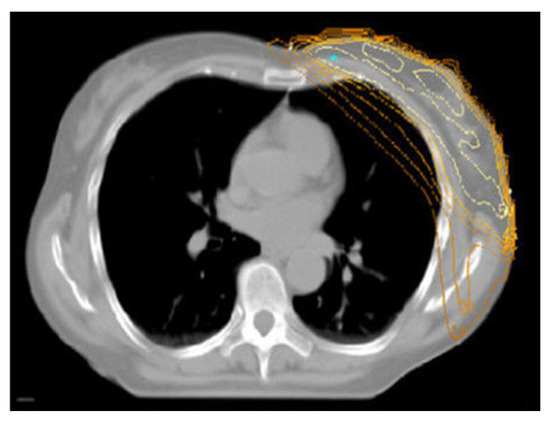

The Prone-Position Whole Breast Irradiation Paradox: Where Do We Stand? A Comprehensive Review

by Chris Monten, Ilaria Benevento, Antonietta Montagna, Edy Ippolito, Paola Anselmo, Luciana Rago, Barbara D’Andrea, Angela Solazzo, Antonella Bianculli, Raffaele Tucciariello, Giammaria Fiorentini, Vito Metallo, Simone Salvago, Carmen Santoro, Anna Vallario and Grazia Lazzari

Over the past two decades, interest in prone-position whole breast irradiation (WBI) as an effective and practical alternative to supine treatment has been growing a lot. Although solid scientific data has provided evidence of substantial dosimetric benefit with decreased toxicity, there is still [...] Read more.

Over the past two decades, interest in prone-position whole breast irradiation (WBI) as an effective and practical alternative to supine treatment has been growing a lot. Although solid scientific data has provided evidence of substantial dosimetric benefit with decreased toxicity, there is still conflict in the radiotherapy community over whether to adopt prone-position WBI as a valid alternative to supine radiotherapy (RT) in routine clinical practice. A large number of prone trials have been conducted to assess and address concerns related to prone treatment in large and pendulous breasts and in left and right breast cancer (BC), nodal irradiation, and its reproducibility with deep inspiration breath hold (DIBH) delivery with photons or protons. Appropriate atlases have been defined to improve prone nodal irradiation. Additionally, more comfortable customized immobilization couches have been constructed to permit IMRT beams and VMAT arrangements with modern LINACs. Although our search in literature databases shows a growing body of evidence from the past two decades on this issue, prone WBI is still underused. Given the paradox of the advances and benefits of this positioning and the lack of drive in the radiotherapy community towards its clinical implementation, the purpose of this comprehensive review is to evaluate the true advantages of this position in real life and contextualize it in scenarios like large breasts, left-sided breast cancer, and nodal irradiation to encourage its implementation in clinical practice. Full article

Show Figures

Figure 1